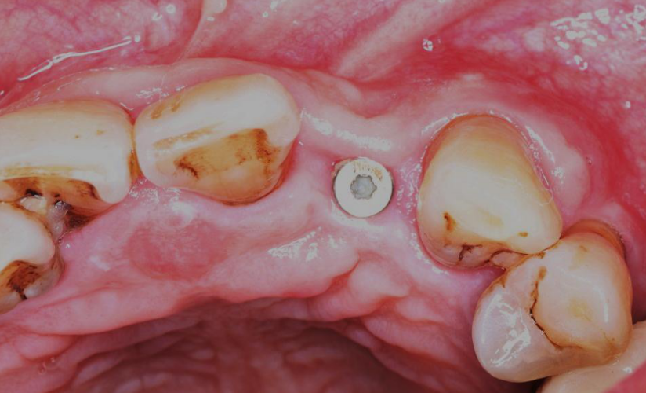

术后8周

牙龈软组织愈合,角化附着龈健康,口腔卫生一般,嘱患者重视日常口腔卫生维护。

术后4.5个月口内照片

术后4.5个月根尖片

ISQ动度值颊舌/近远中为70/73。

术后5个月完成修复

常规印模制取,应患者要求,术后5个月完成修复。